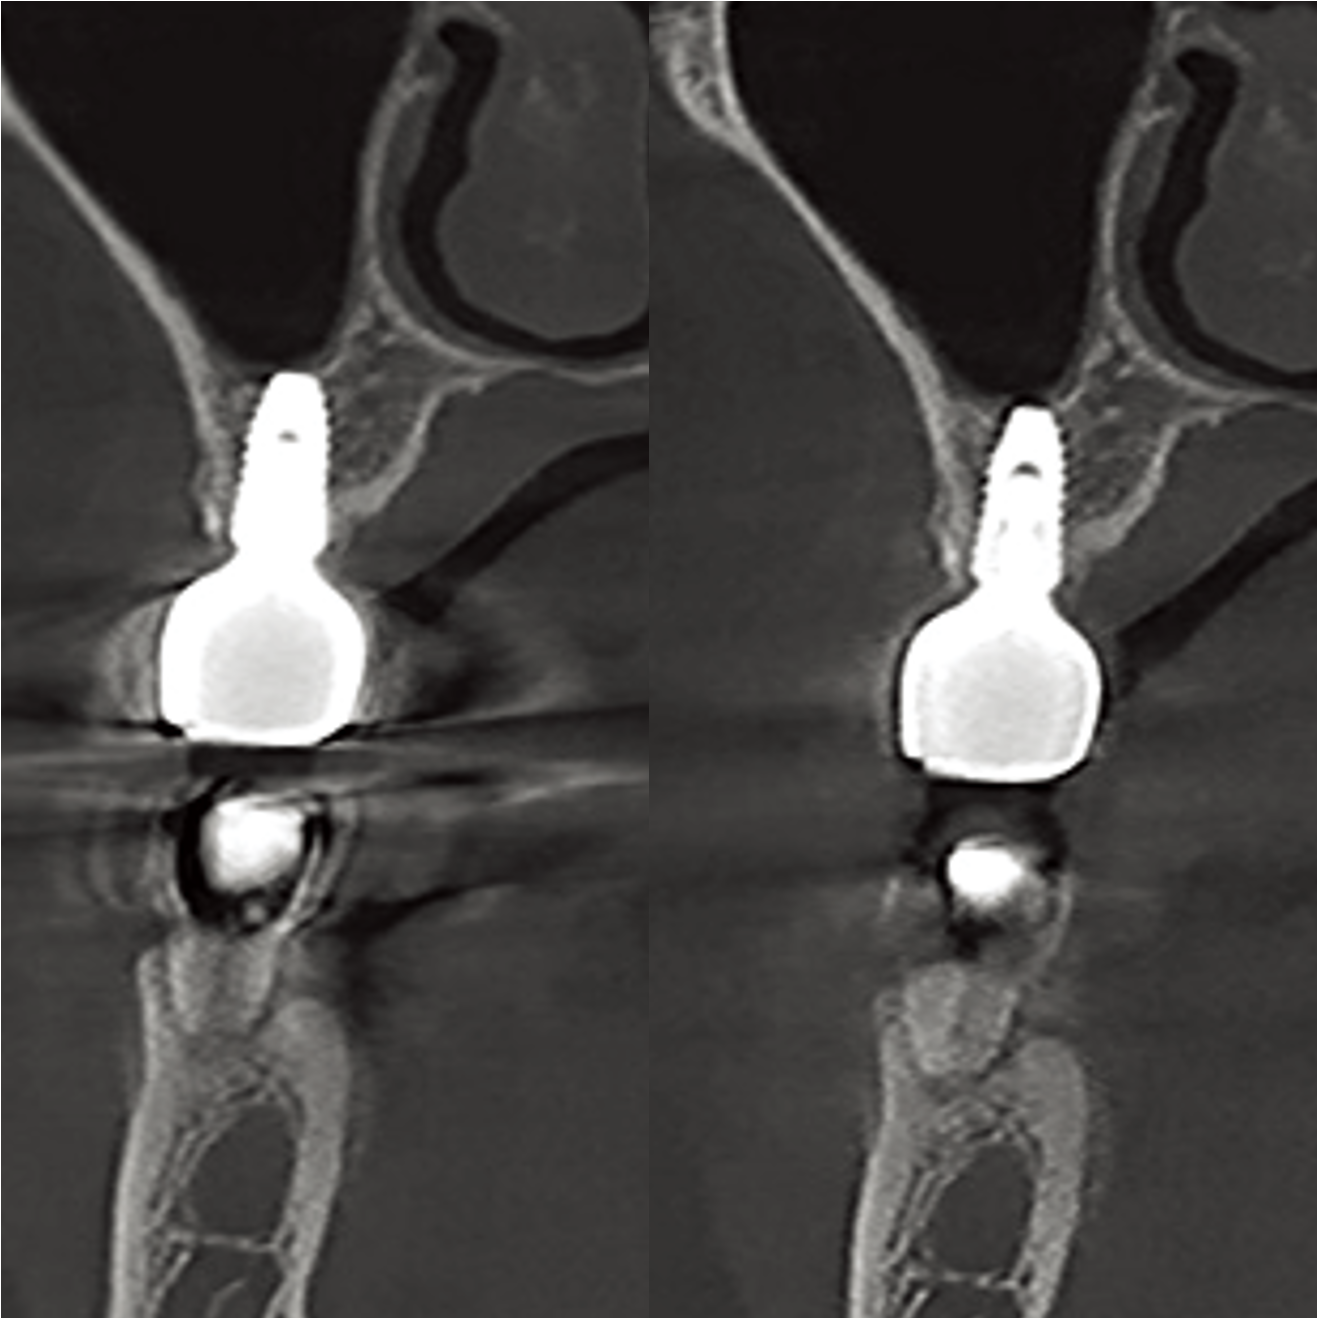

NEXT Level MAR(Metal Artifact Reduction)

The upgraded MAR technology automatically reduces the streak artifacts caused by metal objects and improves the quality of images for precise diagnosis.